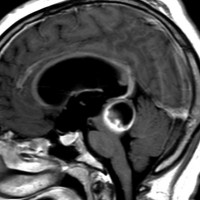

毛様細胞性星細胞腫であり,基本的には初回手術で全摘出できるのですが,現実的には,技術的に難しすぎるので部分摘出で終えることが多いでしょう。この子は,15歳の時に閉塞性水頭症のために,頭痛,嘔吐,意識障害,瞳孔不同となりました。開頭部分摘出術と第3脳室開窓術で回復して,その後にカルボプラチンとビンクリスチンの化学療法を受けました。

でも腫瘍増大が止められずに,発症1年後に54グレイ30分割の放射線治療を受けています。さらにその半年後くらいから再増大しましたが,スードプログレッションと考えられました。上左MRIは放射線治療前,上右MRIは放射線治療1年後です。毛様細胞性星細胞腫は放射線治療後に一過性増大(多くはのう胞性増大)することが多いです。

のう胞性拡大が止まらず,発症3年後にまた再開頭手術 (left occipital transtentorial approach) で亜全摘出しました。右は術後の画像です。初発時の最初の手術で亜全摘出あるいは全摘出 gross total removalできていればと思える例です。